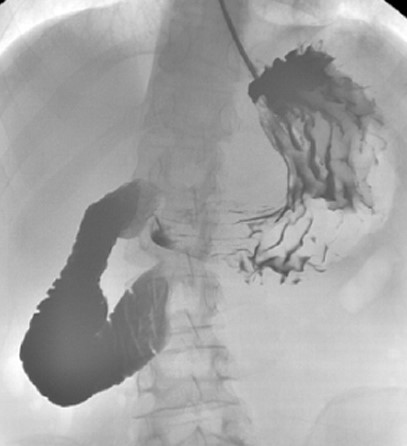

Upper gastrointestinal transit study with gastrografin swallow. Evident obstruction at the third portion of the duodenum. Courtesy Dr. V. Penopoulos.